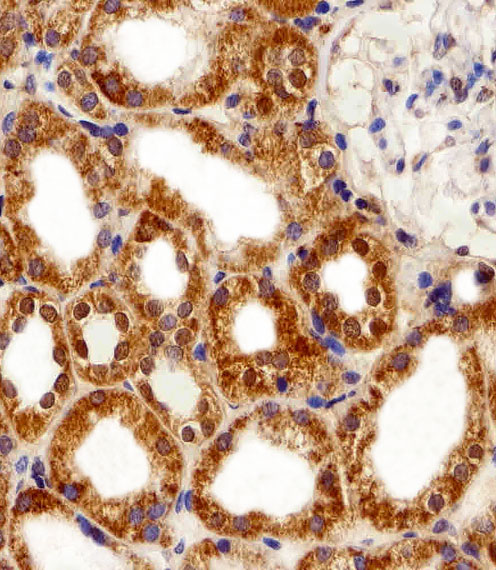

Immunohistochemical analysis of paraffin-embedded H. kidney section using FBXL17 Isoform 2 Antibody (C-term)( APR04628G). APR04628G was diluted at 1:100 dilution. A peroxidase-conjugated goat anti-rabbit IgG at 1:400 dilution was used as the secondary antibody, followed by DAB staining.